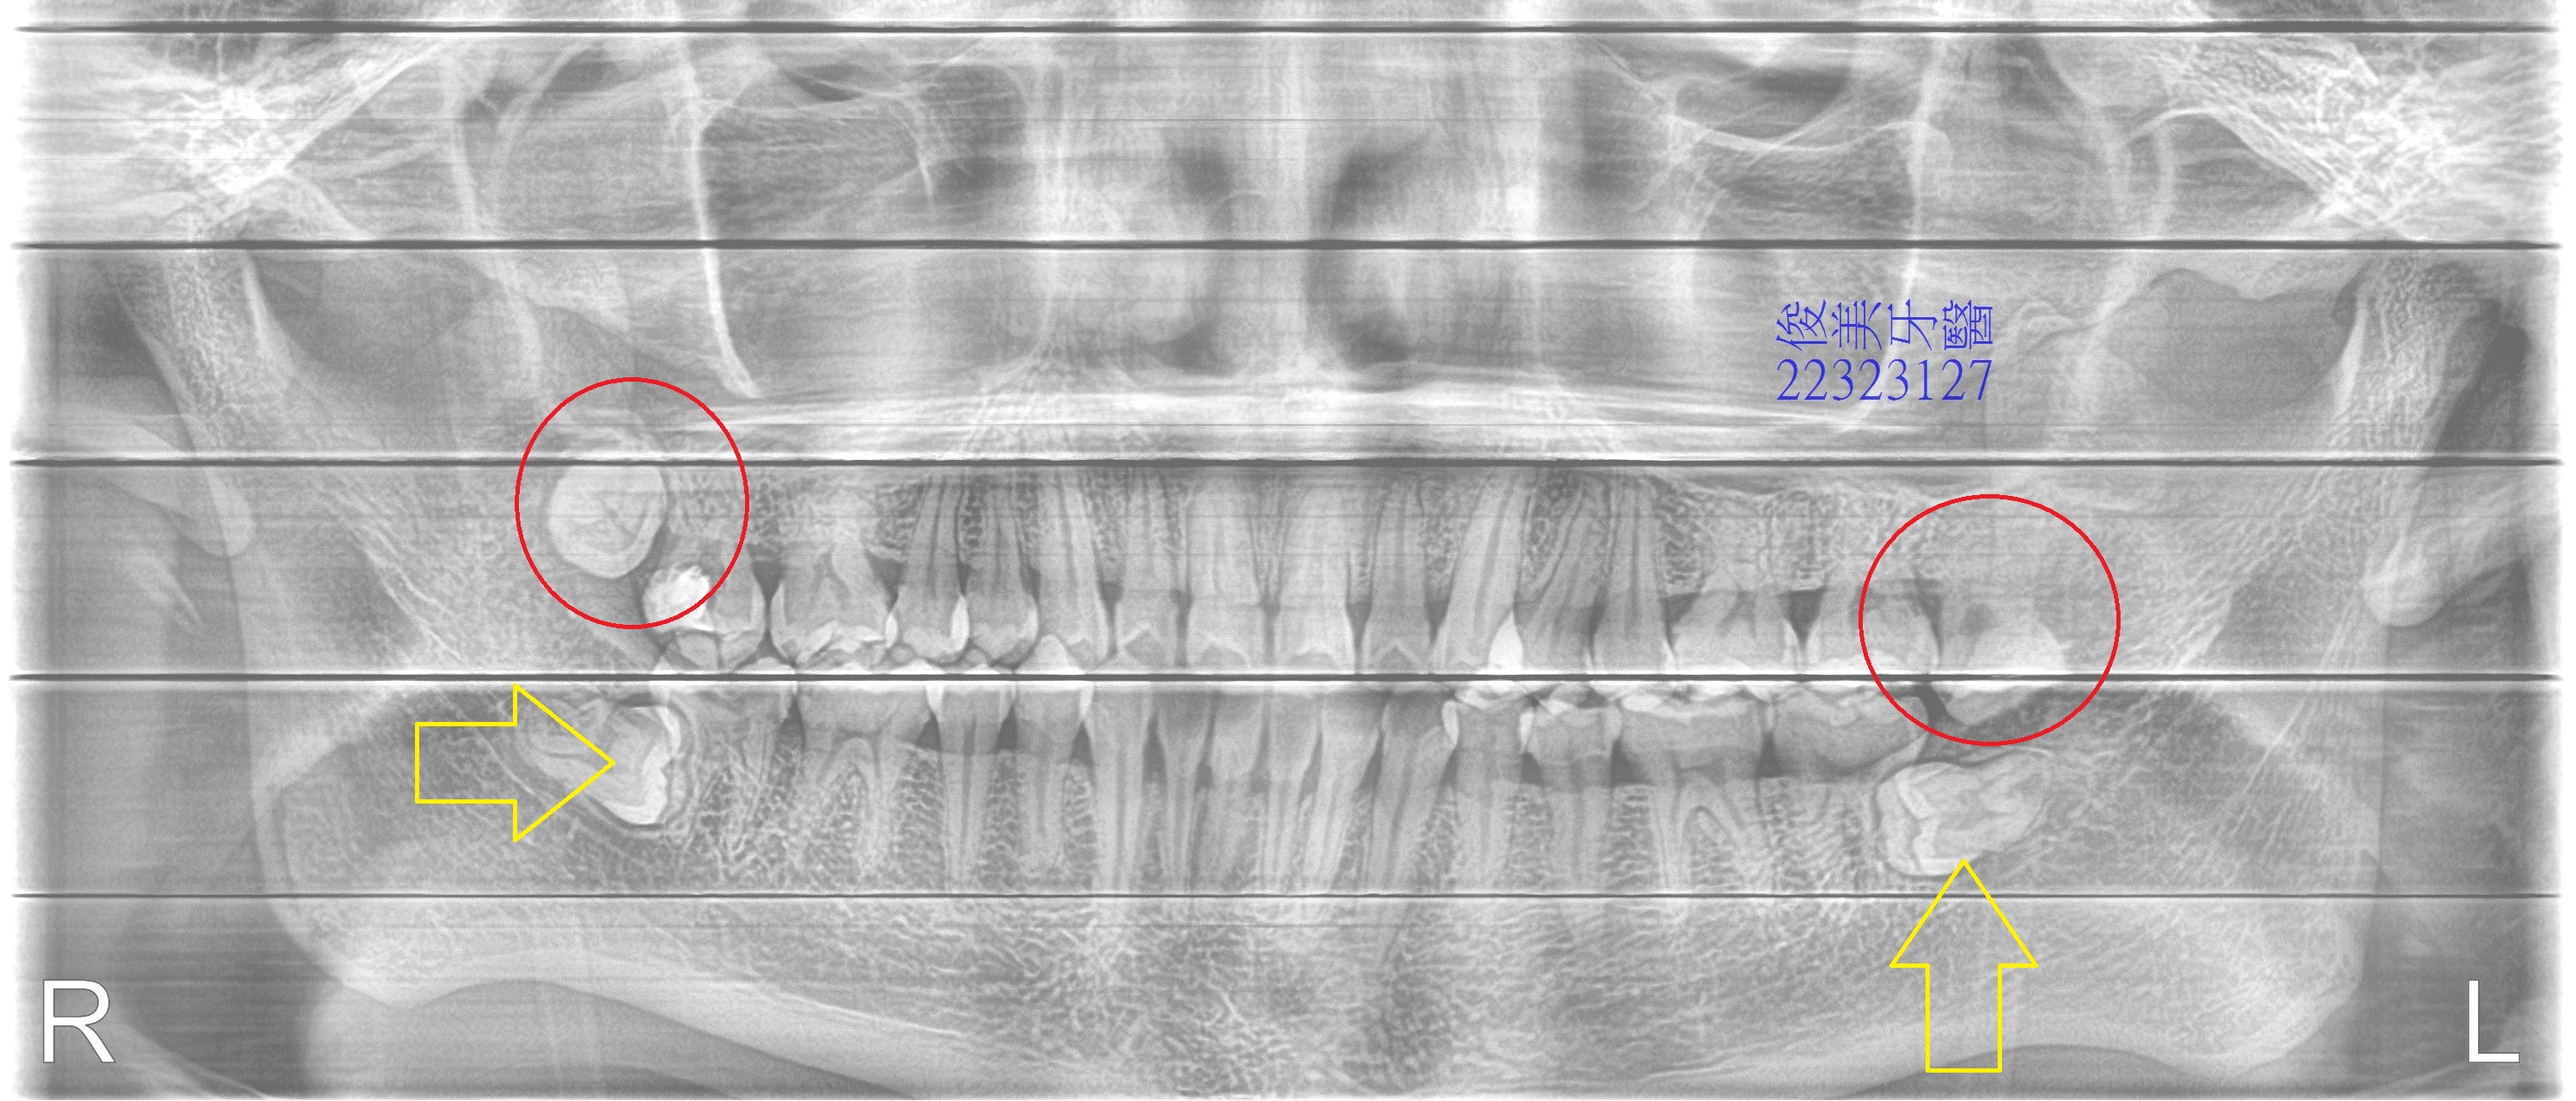

醫師建議他,因智齒不但不好清潔,且造成他牙齒擁擠、重疊,右上第二大臼齒已有很大蛀牙,

雖然表面上補起來 ,但可能會有症狀,因為咬合干擾且不好清潔。

除了將智齒分次拔除以外,需做矯正治療將牙齒的咬合調好,將來就比較不容易有蛀牙或牙周病的問題。

牙根彎曲的很厲害,表示沒有足夠的空間可以生長,

牙齒明顯清潔不良,所以應該要在18歲左右及早處理,以免後患無窮。

口腔內的疾病,不是只有蛀牙而已,蛀牙是一種結果,但往上溯源是咬合干擾、咬合有問題,導致牙縫易塞,最後才產生蛀牙,